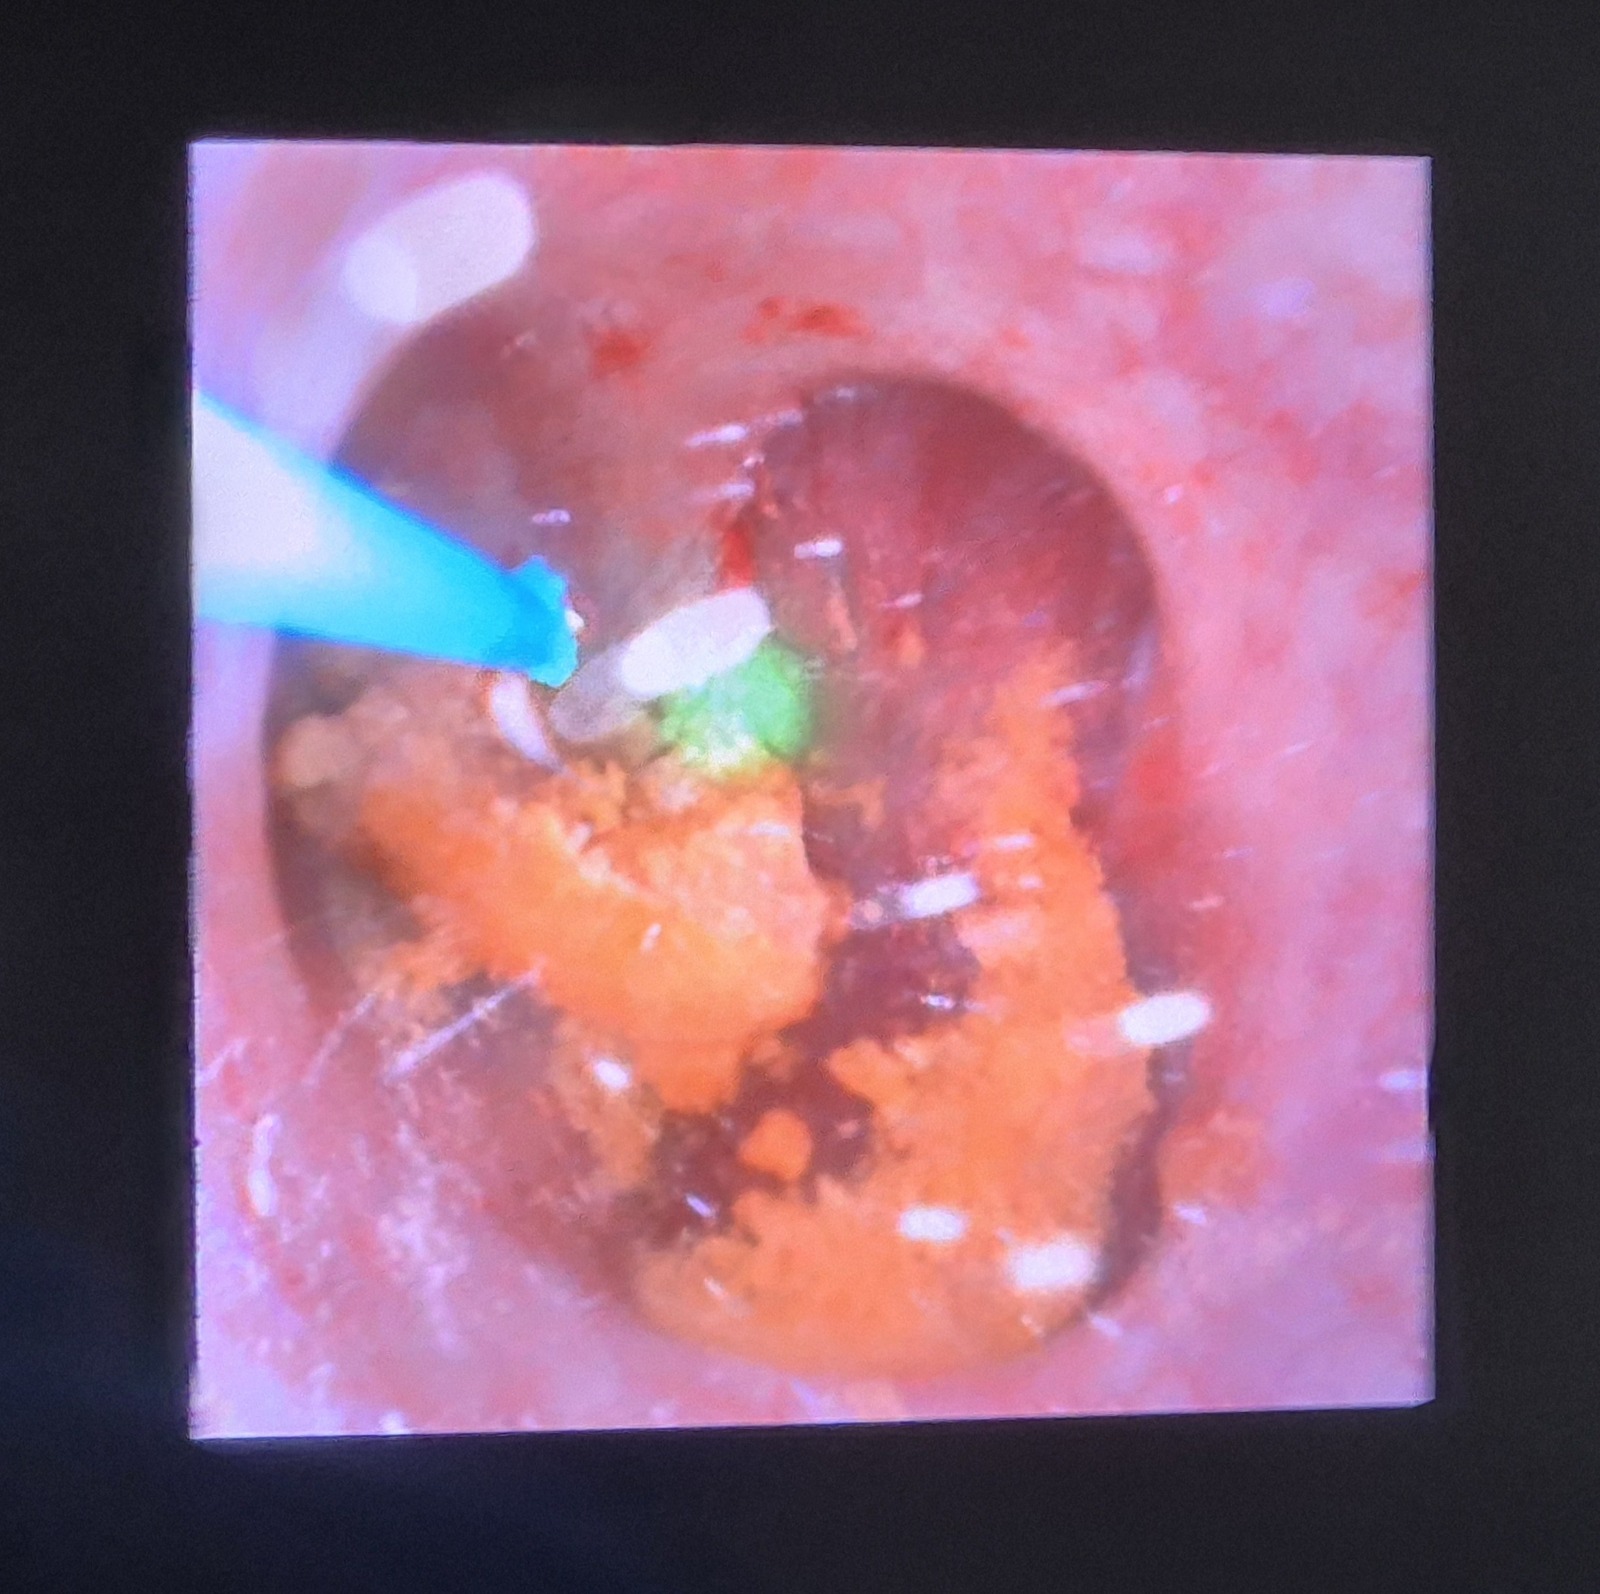

Primele patru intervenții chirurgicale au vizat pacienți diagnosticați cu litiază renală și litiază ureterală – doi bărbați și două femei – și au constat în proceduri de ureteroscopie flexibilă cu litotriție laser. Această metodă modernă permite fragmentarea calculilor renali și ureterali fără incizii chirurgicale, reducând semnificativ riscurile, durerea postoperatorie și perioada de recuperare.